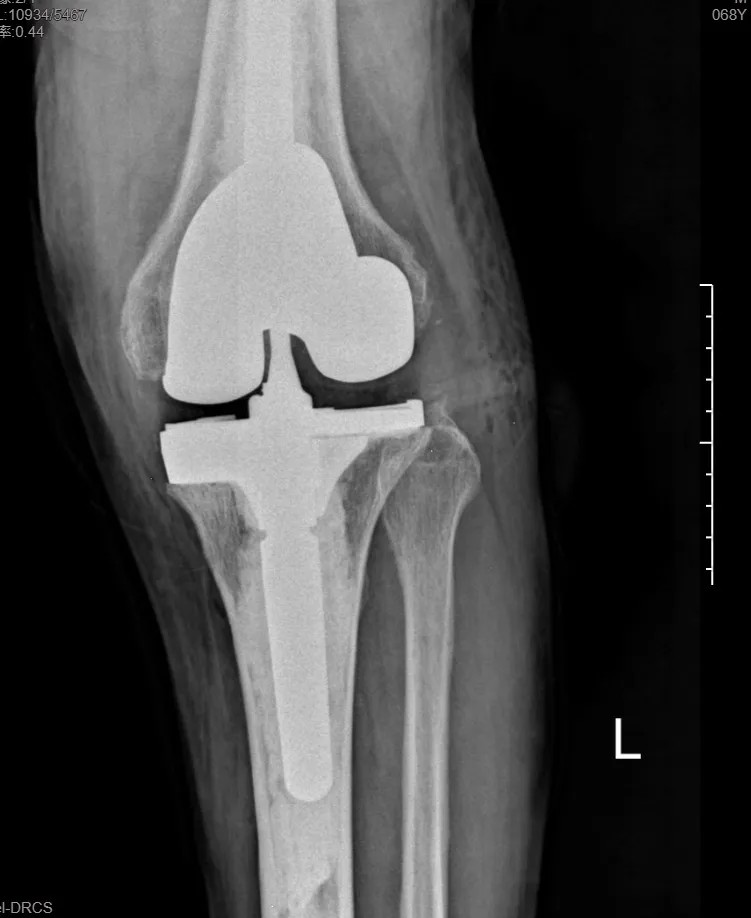

本次手術(shù)的核心,是采用了Evolution® ECCK膝關(guān)節(jié)翻修系統(tǒng)。該系統(tǒng)專為應(yīng)對(duì)翻修手術(shù)中常見的嚴(yán)重骨缺損、韌帶功能不全等極端復(fù)雜情況而設(shè)計(jì)。

其模塊化的組件提供了前所未有的靈活性,就像一套高精度的“工程套件”,允許醫(yī)生在術(shù)中根據(jù)實(shí)際骨缺損情況,自由組合不同尺寸的墊塊、延長(zhǎng)桿等部件,實(shí)現(xiàn)關(guān)節(jié)線和力學(xué)穩(wěn)定性的個(gè)體化重建。

尤為重要的是,該系統(tǒng)保留了內(nèi)軸型假體的設(shè)計(jì)哲學(xué),在重建關(guān)節(jié)穩(wěn)定性的同時(shí),努力模仿了人體膝關(guān)節(jié)自然的運(yùn)動(dòng)方式(內(nèi)軸穩(wěn)定性、外側(cè)活動(dòng)性),旨在讓患者術(shù)后不僅能走,還能走得更舒適、更自然。

集多項(xiàng)前沿科技于一體的精準(zhǔn)手術(shù),帶來了令人欣喜的結(jié)果。術(shù)后第一天,在醫(yī)生指導(dǎo)下,張先生便能夠借助助行器下地站立、邁步行走。

“感覺非常好!膝蓋那里終于不痛了,而且自己能控制它了。”張先生的喜悅之情溢于言表??焖俚墓δ芑謴?fù),極大地增強(qiáng)了他的康復(fù)信心。